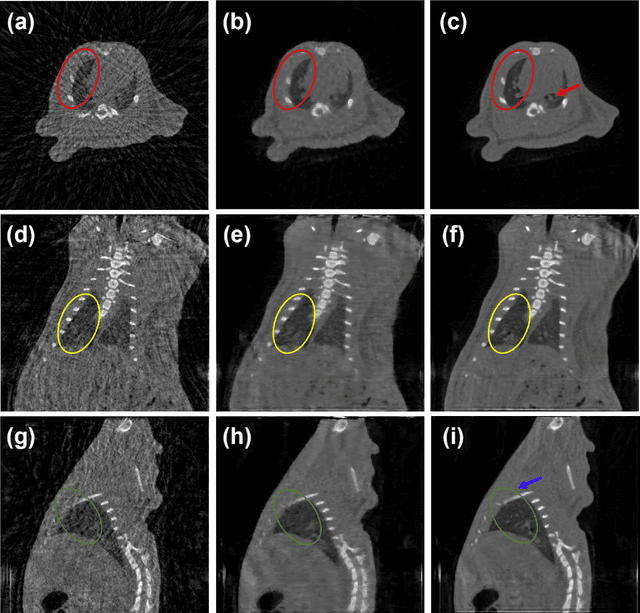

Abstract:Since the invention of modern CT systems, metal artifacts have been a persistent problem. Due to increased scattering, amplified noise, and insufficient data collection, it is more difficult to suppress metal artifacts in cone-beam CT, limiting its use in human- and robot-assisted spine surgeries where metallic guidewires and screws are commonly used. In this paper, we demonstrate that conventional image-domain segmentation-based MAR methods are unable to eliminate metal artifacts for intraoperative CBCT images with guidewires. To solve this problem, we present a fine-grained projection-domain segmentation-based MAR method termed PDS-MAR, in which metal traces are augmented and segmented in the projection domain before being inpainted using triangular interpolation. In addition, a metal reconstruction phase is proposed to restore metal areas in the image domain. The digital phantom study and real CBCT data study demonstrate that the proposed algorithm achieves significantly better artifact suppression than other comparing methods and has the potential to advance the use of intraoperative CBCT imaging in clinical spine surgeries.